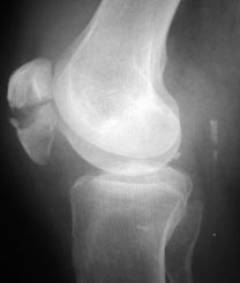

Противопоказания к артроскопии

Абсолютные противопоказания (состояния, при которых хирург однозначно не согласится проводить операцию):

- Костный или фиброзный анкилоз – состояние, при котором суставная щель зарастает костной или плотной соединительной тканью. При этом движения в суставе становятся невозможными. Диагноз можно установить по рентгенограммам.